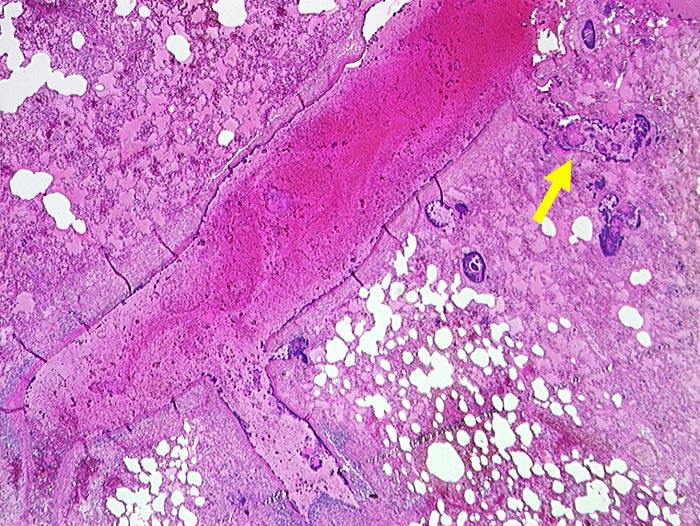

Septische Embolie

Blaue Bakterienhaufen in einem Pulmonalarterienast und im angrenzenden Lungenparenchym. Lungenödem und Hämorrhagien.

Septische Embolien in der Lunge. Nachweis koagulasepositiver Staphylokokken im Blut und im Perikarderguss.

Exzision einer axillären Pyodermie (wahrscheinlich Furunkel) durch den Patienten selbst vor 10 Tagen. Staphylokokkus aureus Sepsis. Septisch toxischer Schock mit Herzstillstand.

Die Mortalität bei Staphylokokkensepsis mit Pneumonie beträgt über 80%.